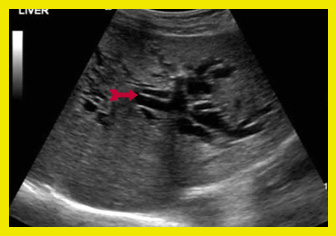

| תצלום 3.8: הרחבת צינור המרה המשותף, בסונר משמאל החיצים מצביעים על צינור המרה המורחב. | |

בדיקת האולטרה-סאונד היא מכשיר עזר חשוב באבחון הלוקים באבנים בכיס המרה, בצהבת או במצבים דלקתיים חריפים. אמינות הבדיקה היא גבוהה - 95%. בבדיקה זו מודגמות האבנים בכיס המרה כנקודות בהירות שמאחוריהן "צל אקוסטי" (Acoustic shadow) - אזור בלא החזרת קול (האבן חוסמת את הקול) (תצלום 1.8). אם הנבדק משנה תנוחה, האבן זזה, והדבר מודגם בבדיקה. אבנים בדרכי המרה ניתנות להדגמה ב- 20% מהמקרים. דרכי מרה מורחבות אפשר להדגים בלוקים בחסימה בדרכי המרה. בחולים אלה ההרחבה יכולה להיות של דרכי המרה החוץ ו\או התוך-כבדיות. (תצלום 2.8 ו- 3.8). נוזל סביב כיס המרה ודופן מעובה של כיס המרה מעידים על דלקת של כיס המרה (תצלום 4.8). אפשר לבצע בדיקת אולטרה-סאונד של דרכי המרה בזמן הניתוח ולאתר אבנים בדרכי המרה.

אולטרה-סאונד אנדוסקופי (EUS): ה-EUS הינה בדיקת US אנדוסקופית המבוצעת דרך אנדוסקופ בסמוך לאיבר הנבדק. גישה זו מאפשרת לראות את אנטומיה ופתולוגיה של דרכי המרה בצורה ברורה. הבדיקה מבוצעת כיום בכל חולה עם הרחבה של דרכי מרה או הפרעה בתפקודי כבד הרומזת לתהליך חסימתי בדרכי המרה (תצלום 5.8).